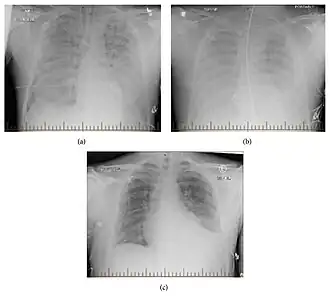

Within 4-10 days of infection, patients may begin to experience severe respiratory symptoms as the infection progresses.[7] These symptoms can include cough, shortness of breath, tightness of the chest, and rapid onset of pulmonary edema. Fluid buildup in the lungs caused by vascular leakage via viral disruption of endothelial blood vessel cells can lead to respiratory failure if untreated.[7]